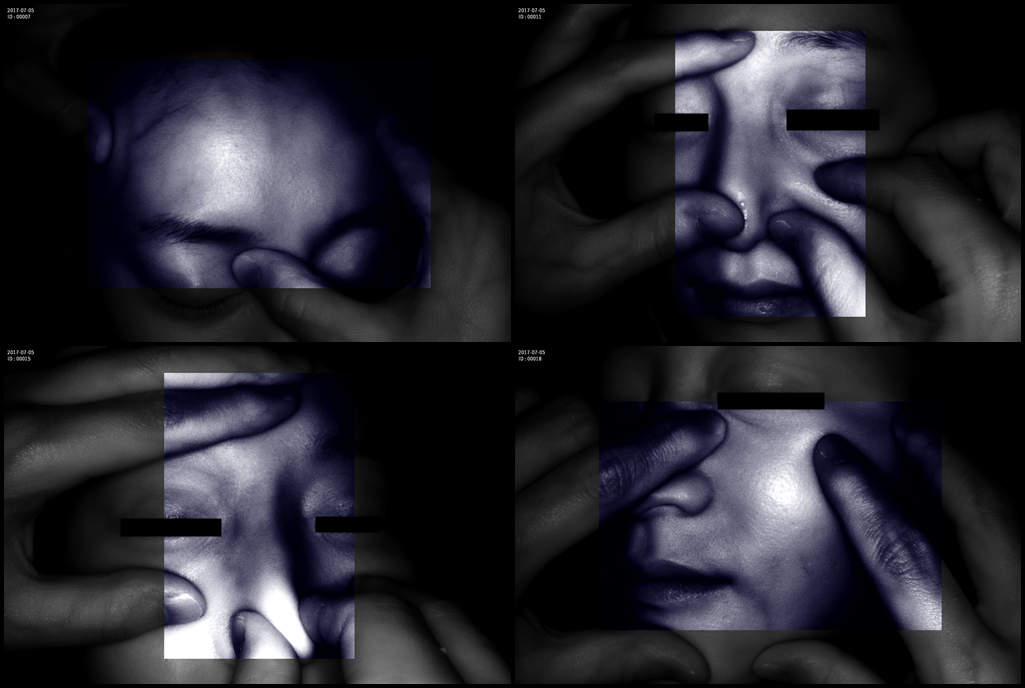

Grad mare de detecție a venelor greu vizibile până la 10 mm adâncime (inclusiv vene faciale)

Funcție de salvare și comparare imagini înainte și după procedura de tratament vascular

Imaginea venelor este proiectată pe monitorul propriu în timp real si ajută la identificarea corectă și precisă